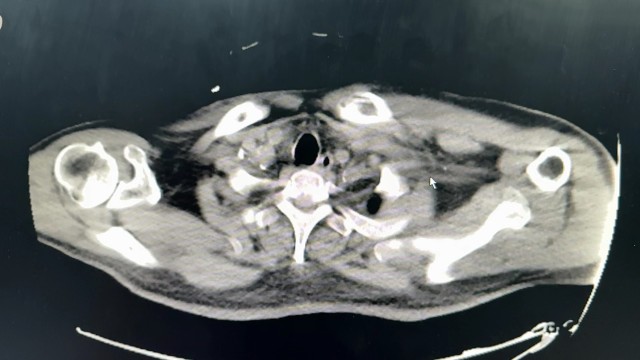

西地兰vip普外科医师

文/西地兰 特别声明:所有观点仅代表个人言论 特别声明:与当事双方均无利益相关 山东男孩,目前全网沸沸扬扬,看过一些观点,直言不讳地说,大多偏颇。要么一股脑地指责医方的全责,甚至有说千万别在县医院看病。要么又为医方无休止的遮羞,认为这样的手术在县医院做下来已经非常了不起。而我想到的是,以后面临类似的病例,我们怎么办?那么我们不如来一次专业的病案讨论。既然是事后讨论,难免有事后诸葛亮的感觉,但是假如下一次,同行们遭遇这样的病例,如何处置?这是医疗行业所面临的问题。希望我整理的这些思路和相关病例,对同行们有所帮助!就目前的资讯外界不足以判断是否需要急诊,如果需要急诊,那么只能根据术中所见进行处理,

智商不太富裕 回复

目前知道的消息,第一,术前发现一个血肿,然后做增强CT发现一个占位,没说血肿与肿瘤的关系,术后病理没有描述肿瘤出现破裂出血,大概率就一个小血肿,我就不明白当地主任凭哪个指针去给这小孩开急诊刀的?哪个指南告诉他需要急诊开?第二,诊断不明确他想的不是进一步检查,一边观察一边进一步查,他反而选择腹腔镜探查,这个探查的指针在哪?第三,腹腔一个血肿,没有活动性出血,没有血压心率出现问题,为什么要开腹进去碰它?不能等血肿吸收再明确肿瘤性质吗?第四,1点进腹,3点病理结果出来,按这个时间还算顺利,应该还没出事,孩子还算平稳,病理是低度恶性,切了就治愈,他一年能开几台这手术,就敢继续做,拿孩子练手。第五,后面